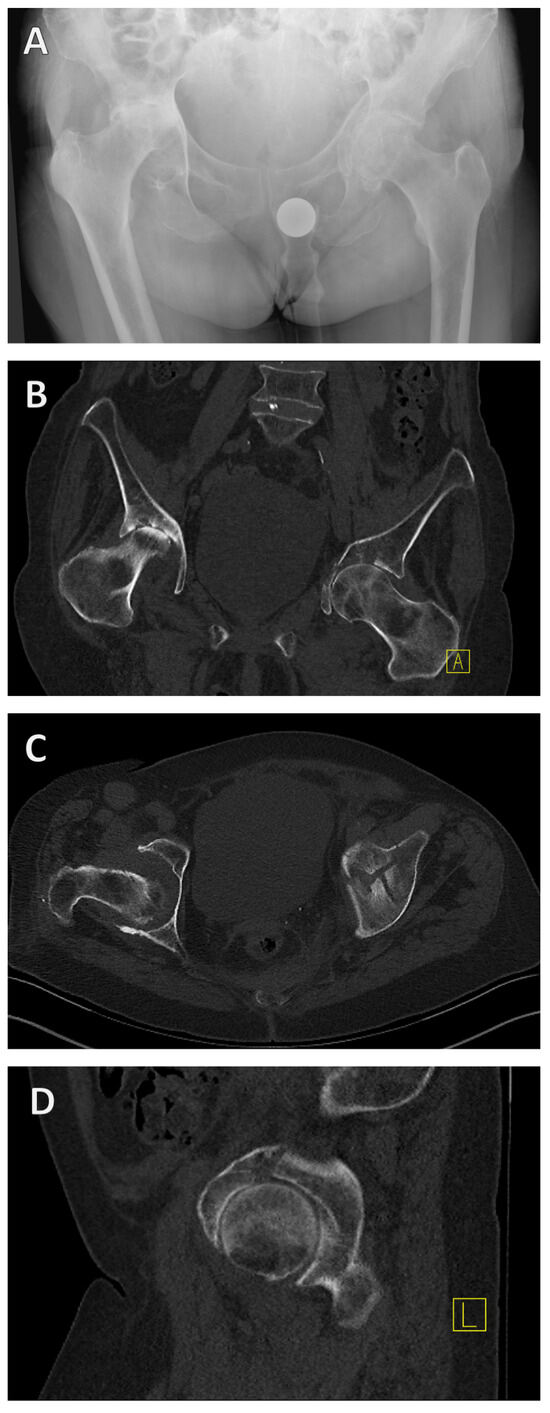

Alongside medical history and physical examination, radiological imaging techniques play a key role in the diagnosis of acetabular fractures. Both X-ray examination in the anterior–posterior, ala, and obturator beam of the pelvis and CT are used as standard procedures and are highly recommended [27] (Figure 3).

If an acetabular fracture cannot be ruled out with certainty in the X-ray examination, a CT scan should be performed. CT is not only used to confirm the diagnosis but also to categorize the fracture as described above (Figure 3B–D). CT can therefore be used to categorize the fracture and plan the surgical treatment. It is important to know the classification, as the approach is determined in the planning phase after the diagnosis and categorization.

Figure 3. X-ray and CT diagnosis of a geriatric acetabular fracture. Initially, the left-sided acetabular fracture can be recognized in the anterior–posterior radiograph of the pelvis (A). A CT scan was added for fracture classification and preoperative planning (BD). It revealed a T-shape fracture (BD).